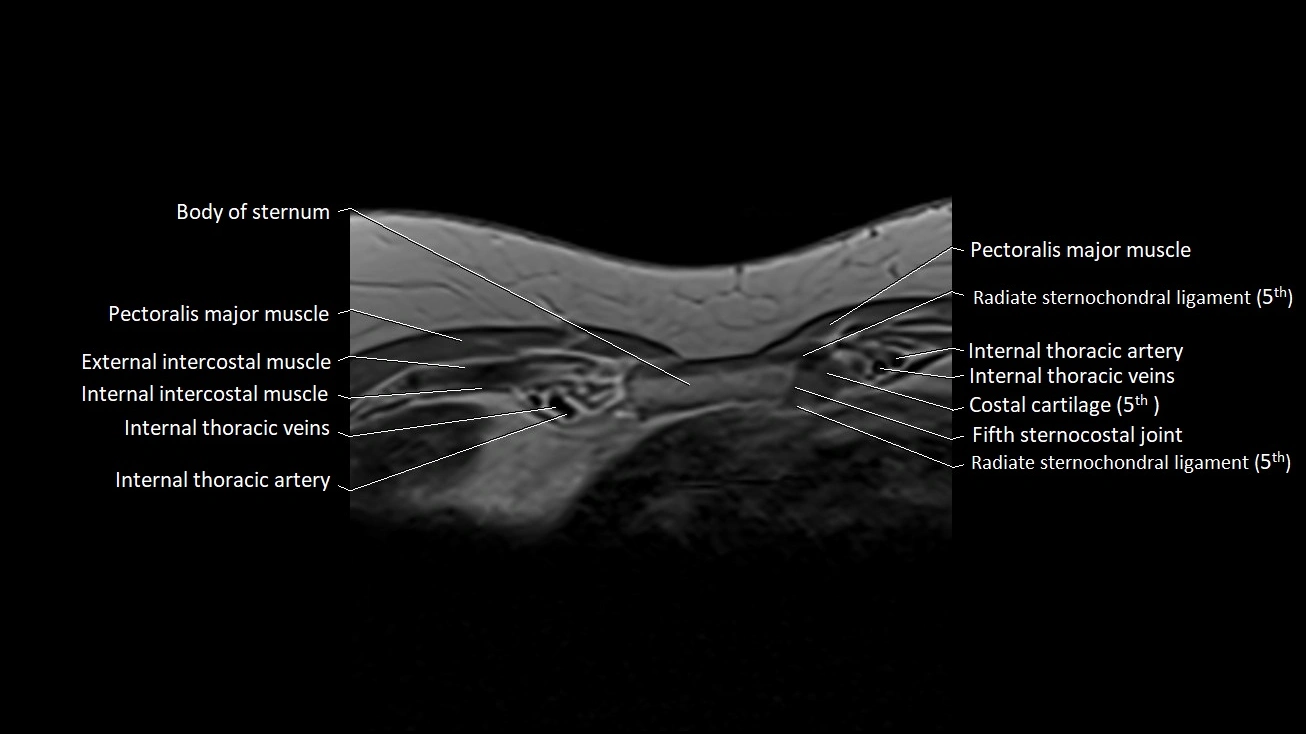

MRI images

image